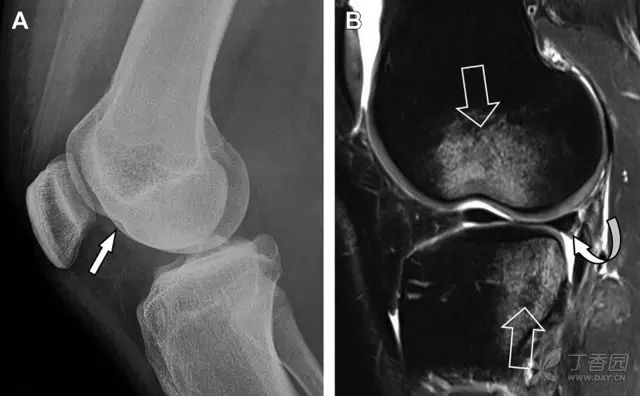

涉及到三角韧带和外侧副韧带(LCL)的复杂性骨折常常不难发现,尤其是存在表面软组织肿胀时。然而,后胫腓韧带牵拉引起的胫骨后踝骨折则很难发现。这些骨折大小不一(图 2),却很重要,因为他们常与胫骨远端螺旋骨折有关,或者是三踝骨折的一部分。

图 2 胫骨后踝骨折。A 侧位片示来源于胫骨后踝的一个小骨折碎片(箭头),因踝部扭伤导致;B 另一位跖屈损伤的患者,侧位片示一个大骨折块(箭头)

Tillaux 骨折,是足外旋外展时,胫腓前韧带牵拉引起的一种胫骨结节撕脱性骨折。斜位片上可见典型表现(图 3)。

图 3 摔倒后胫骨结节骨折。A 正位片示一细小斜型骨折线(箭头);B 侧位片示正常;C 冠状位 CT 三维成像更清晰地显示了骨折线和骨折块大小(空箭头);D 矢状位 CT 多维重建图像示骨折位置(箭头)

距骨外侧突骨折常因踝外翻背屈时,跟骨上外侧面撞击距骨外侧突下缘导致,或偶尔由踝内翻引起,被称为「滑雪板者骨折」。这种骨折只能在踝关节正位片上发现,而且外踝远端表面软组织肿胀往往是一个重要线索(图 4)。

图 4 距骨外侧突骨折。A 正位片示内翻损伤所致的距骨外侧突撕脱性骨折(箭头);B 另一位患者,踝外翻损伤导致典型的「滑雪板者骨折」,X 片上可见一较大的三角形骨折块(方框);C 第二位患者的 MRI 矢状位 T1 加权像示横行骨折(箭头)